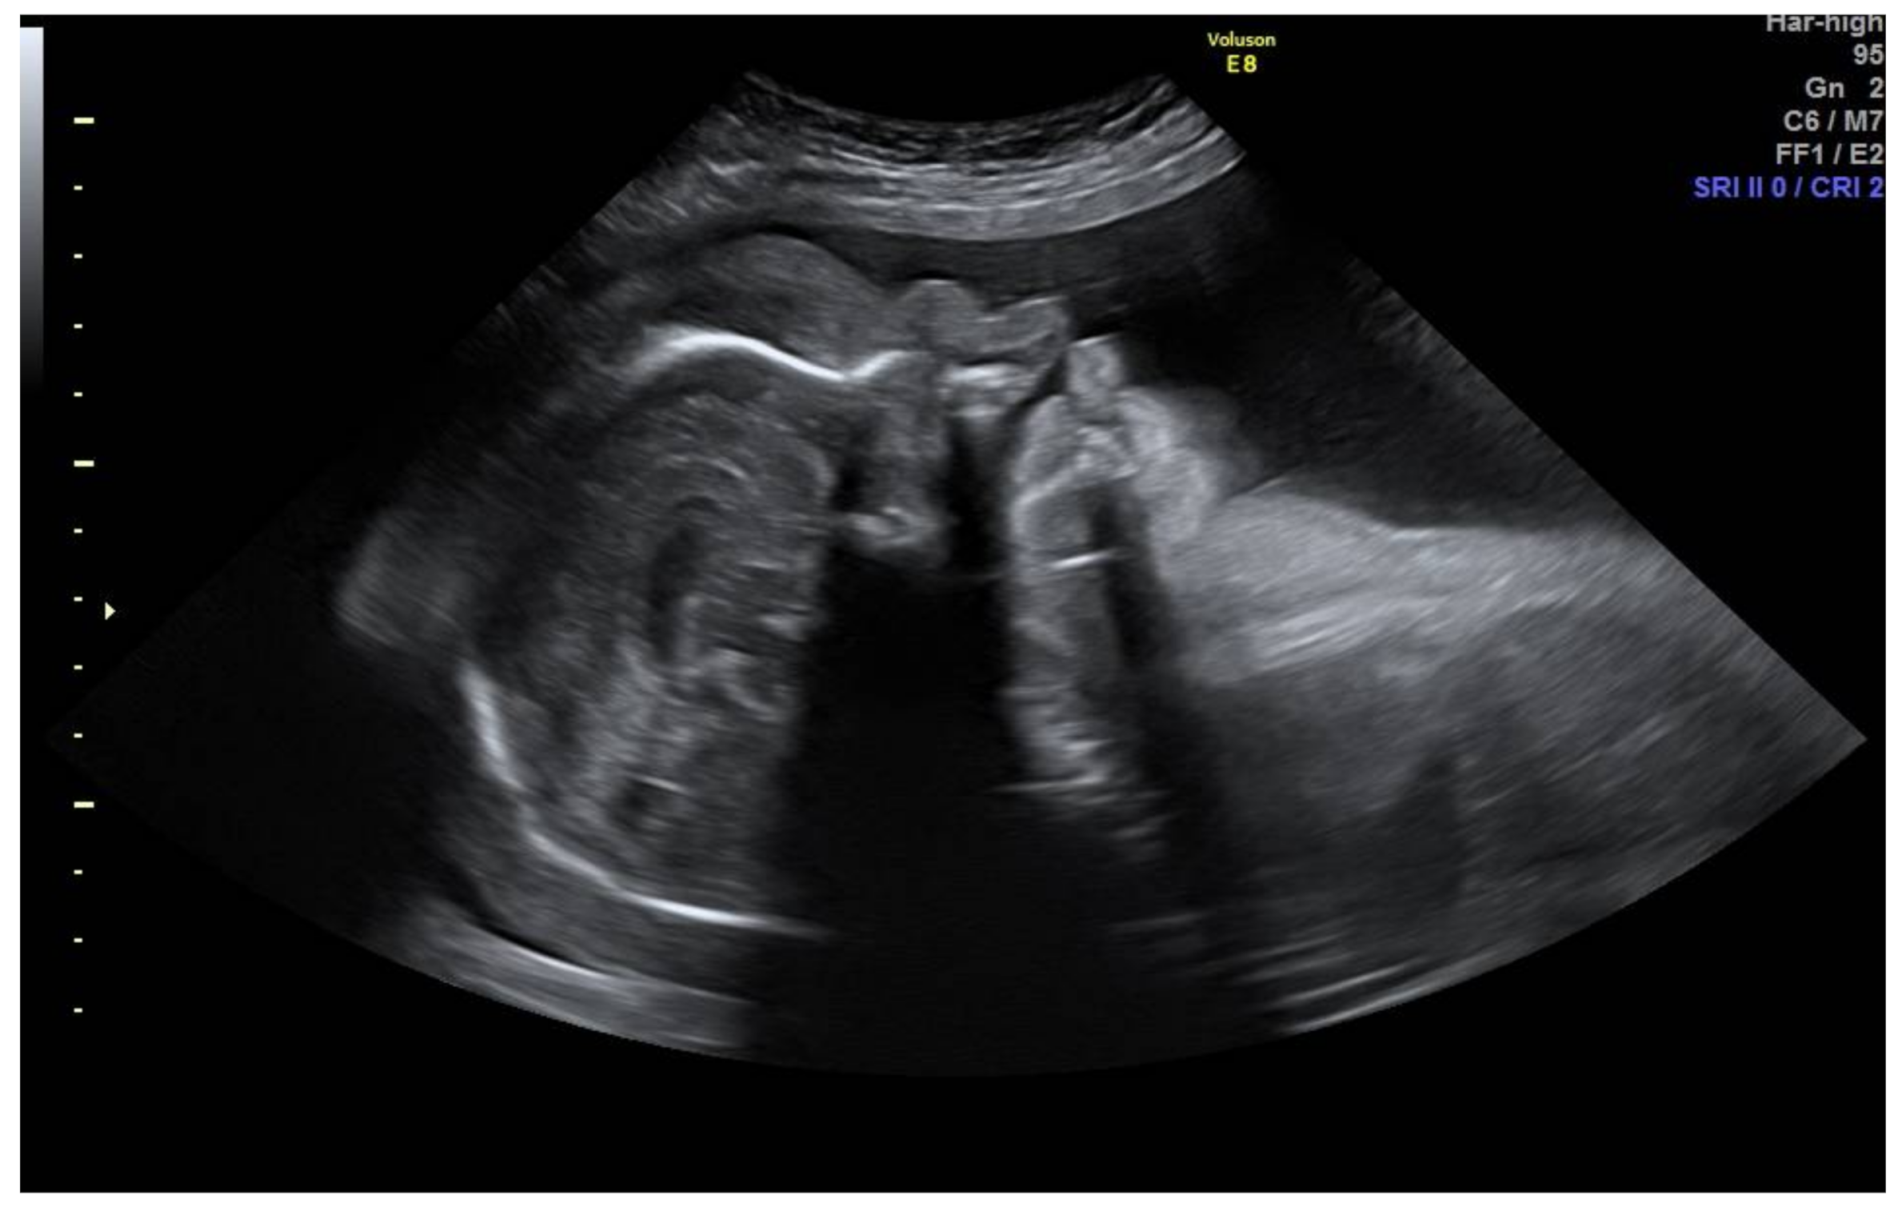

2. Case Presentation